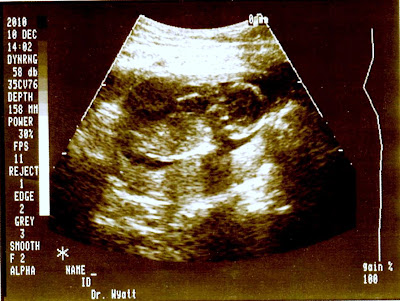

My mom made it up to visit with us this week to see my “belly” grow. She is planning on coming up every two months to see the progression and help us get ready for this little one. Luckily, she was able to come to meet Dr. Wyatt and even got to see the baby when we got our latest ultrasound. Thankfully the baby is starting to look more like a human and not so much like a seahorse. Also on the agenda was to make our way to Babies ‘R Us to start our baby registry. Boy, I had no idea that something so little would need so much! It was so funny to Lucas and I because we thought that registering for our wedding was bad enough because there was just so much to choose from. Doing a baby registry is worse because there are just as much things, but now you have to take in account safety, remembering that less is more and not registering for things that we don’t need. I can’t wait until the nesting stage kicks in and we can put the baby’s room together, though I’m sure Duke and Harley aren’t very excited to see their space and room taken over by the baby.

Thanks for a great visit! I'm telling you, when Dr. Wyatt was doing the ultrasound…..baby turned its head to us and smiled. So cool! Baby even raised its little arm to say…..here I am! Enjoyed my time with Duke and Harley too…..the best dogs ever! See you in February! Love you!